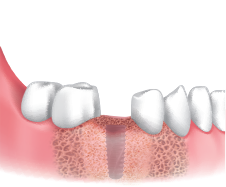

A Clinical Case using Ø3.5/4.0 Harvesting Drill

by Dr. Soohong Kim, DDS, Ph.D

-

Drilling at 300 rpm with irrigation was carried out after marking implant and harvesting position.

The Silicone Shield was brought into close contact with various types of bone level and prevented bone chip loss.

The amount of bone taken was easily ascertained, through the transparent Silicone Shield.

The bone was transferred to bone dish after disassembling the Silicone Shield and Stopper.

The amount of the bone was much more than expected.

After the implant placement, healing abutments were connected and carried out GBR in the defected area.

* 2 Step Harvesting : Drilling to 7mm is recommended after transferring bone chips to bowl since the Stopper & Silicone Shield are fully filled with bone chips while 4mm drilling.